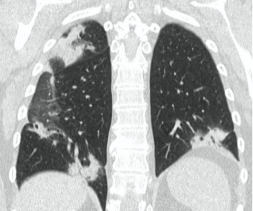

2. Наличие клинических проявлений, указанных в п. 1, в сочетании с характерными изменениями в легких по данным компьютерной томографии (КТ) (см. Приложение 1 настоящих рекомендаций) вне зависимости от результатов однократного лабораторного исследования на наличие РНК SARS-CoV-2 и эпидемиологического анамнеза.

- Изменения при КТ (рентгенографии), типичные для вирусного поражения (объем поражения минимальный или средний; КТ 1 - 2)

- Изменения в легких при КТ (рентгенографии), типичные для вирусного поражения (объем поражения значительный или субтотальный; КТ 3 - 4)

- Изменения в легких при КТ (рентгенографии), типичные для вирусного поражения критической степени (объем поражения значительный или субтотальный; КТ 4) или картина ОРДС.